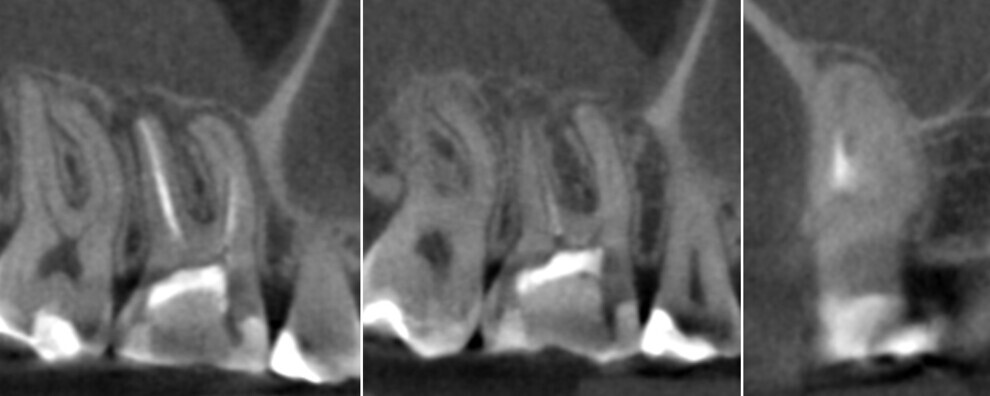

Figs. 1a–c. (All images: Bartłomiej Karaś and Grzegorz Witkowski)

A 28-year-old female patient was referred to Dr Karaś’s office because the previous dentist was not able to locate the orifice of the second mesiobuccal (MB2) canal in tooth #16. Owing to her medical history, endodontic treatment was performed, the tooth being symptomatic. A CBCT scan was performed in order to examine the mesial root and create a treatment plan. The shape of the root and the widening of the periodontal ligament indicated a separate path and apical foramen of an MB2 canal. Also, the slice showing the palatal part of the MB root revealed a small path, suggesting the presence of an MB2 canal. There were also visible signs of inflammation around the apices of the MB and distobuccal (DB) root and in the membrane of the maxillary sinus (Fig. 1).